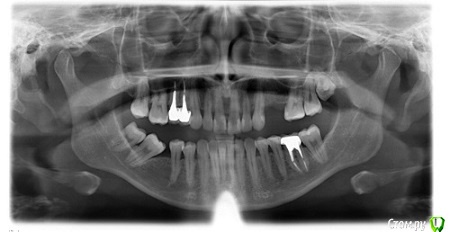

Alessa Опубликовано 28 февраля, 2021 Автор Поделиться Опубликовано 28 февраля, 2021 (изменено) у вас будет капа на интрузию? Или серия кап?Если движения не будет, а это будет просто маскировка - то нет, не помешает приживлению импланта. Если будет движение заложено - то возможно. Интрузия это вообщем то агрессивное перемещениеспасибо большое за ответ!Хочу чисто для маскировки.А если имплант уже приживется полностью, тогда интрузию можно делать? Я хочу имплант поставить с консольным протезом и вернуться к нормальной жизни, и снова улыбаться нормально плюс в этом году скорее всего перееду в другой город, так что скорее всего ортодонтическое лечение все-таки начинать не буду пока. Ходила к 4 ортодонтам, у всех разное мнение, но послушать Врачей это я люблю)Эстетика улыбки не беспокоит. Вот только всю жизнь глубокий прикус и лет 10 сустав щелкает иногда, если рот пытаюсь широко открыть, но если челюсть выдвинуть влево, то щелчка не будет вовсе. Хотелось бы исправить и прикус и сустав на место поставить, вот только боюсь, что всё это затянется на долгие годы. Фото зубовhttps://a.radikal.ru/a17/2102/cf/5713a7304f53.jpg Изменено 28 февраля, 2021 пользователем Alessa Ссылка на комментарий